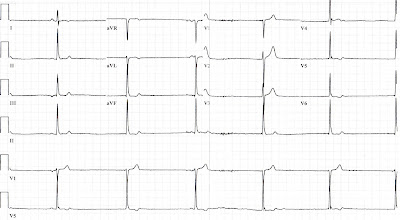

First, how should we consider a patient who adamantly denies any chest pain/pressure (or back pain, shoulder aches, or jaw discomfort...), but has an ECG that looks like this:

![]() |

| True story. Yeah, it was an RCA. |